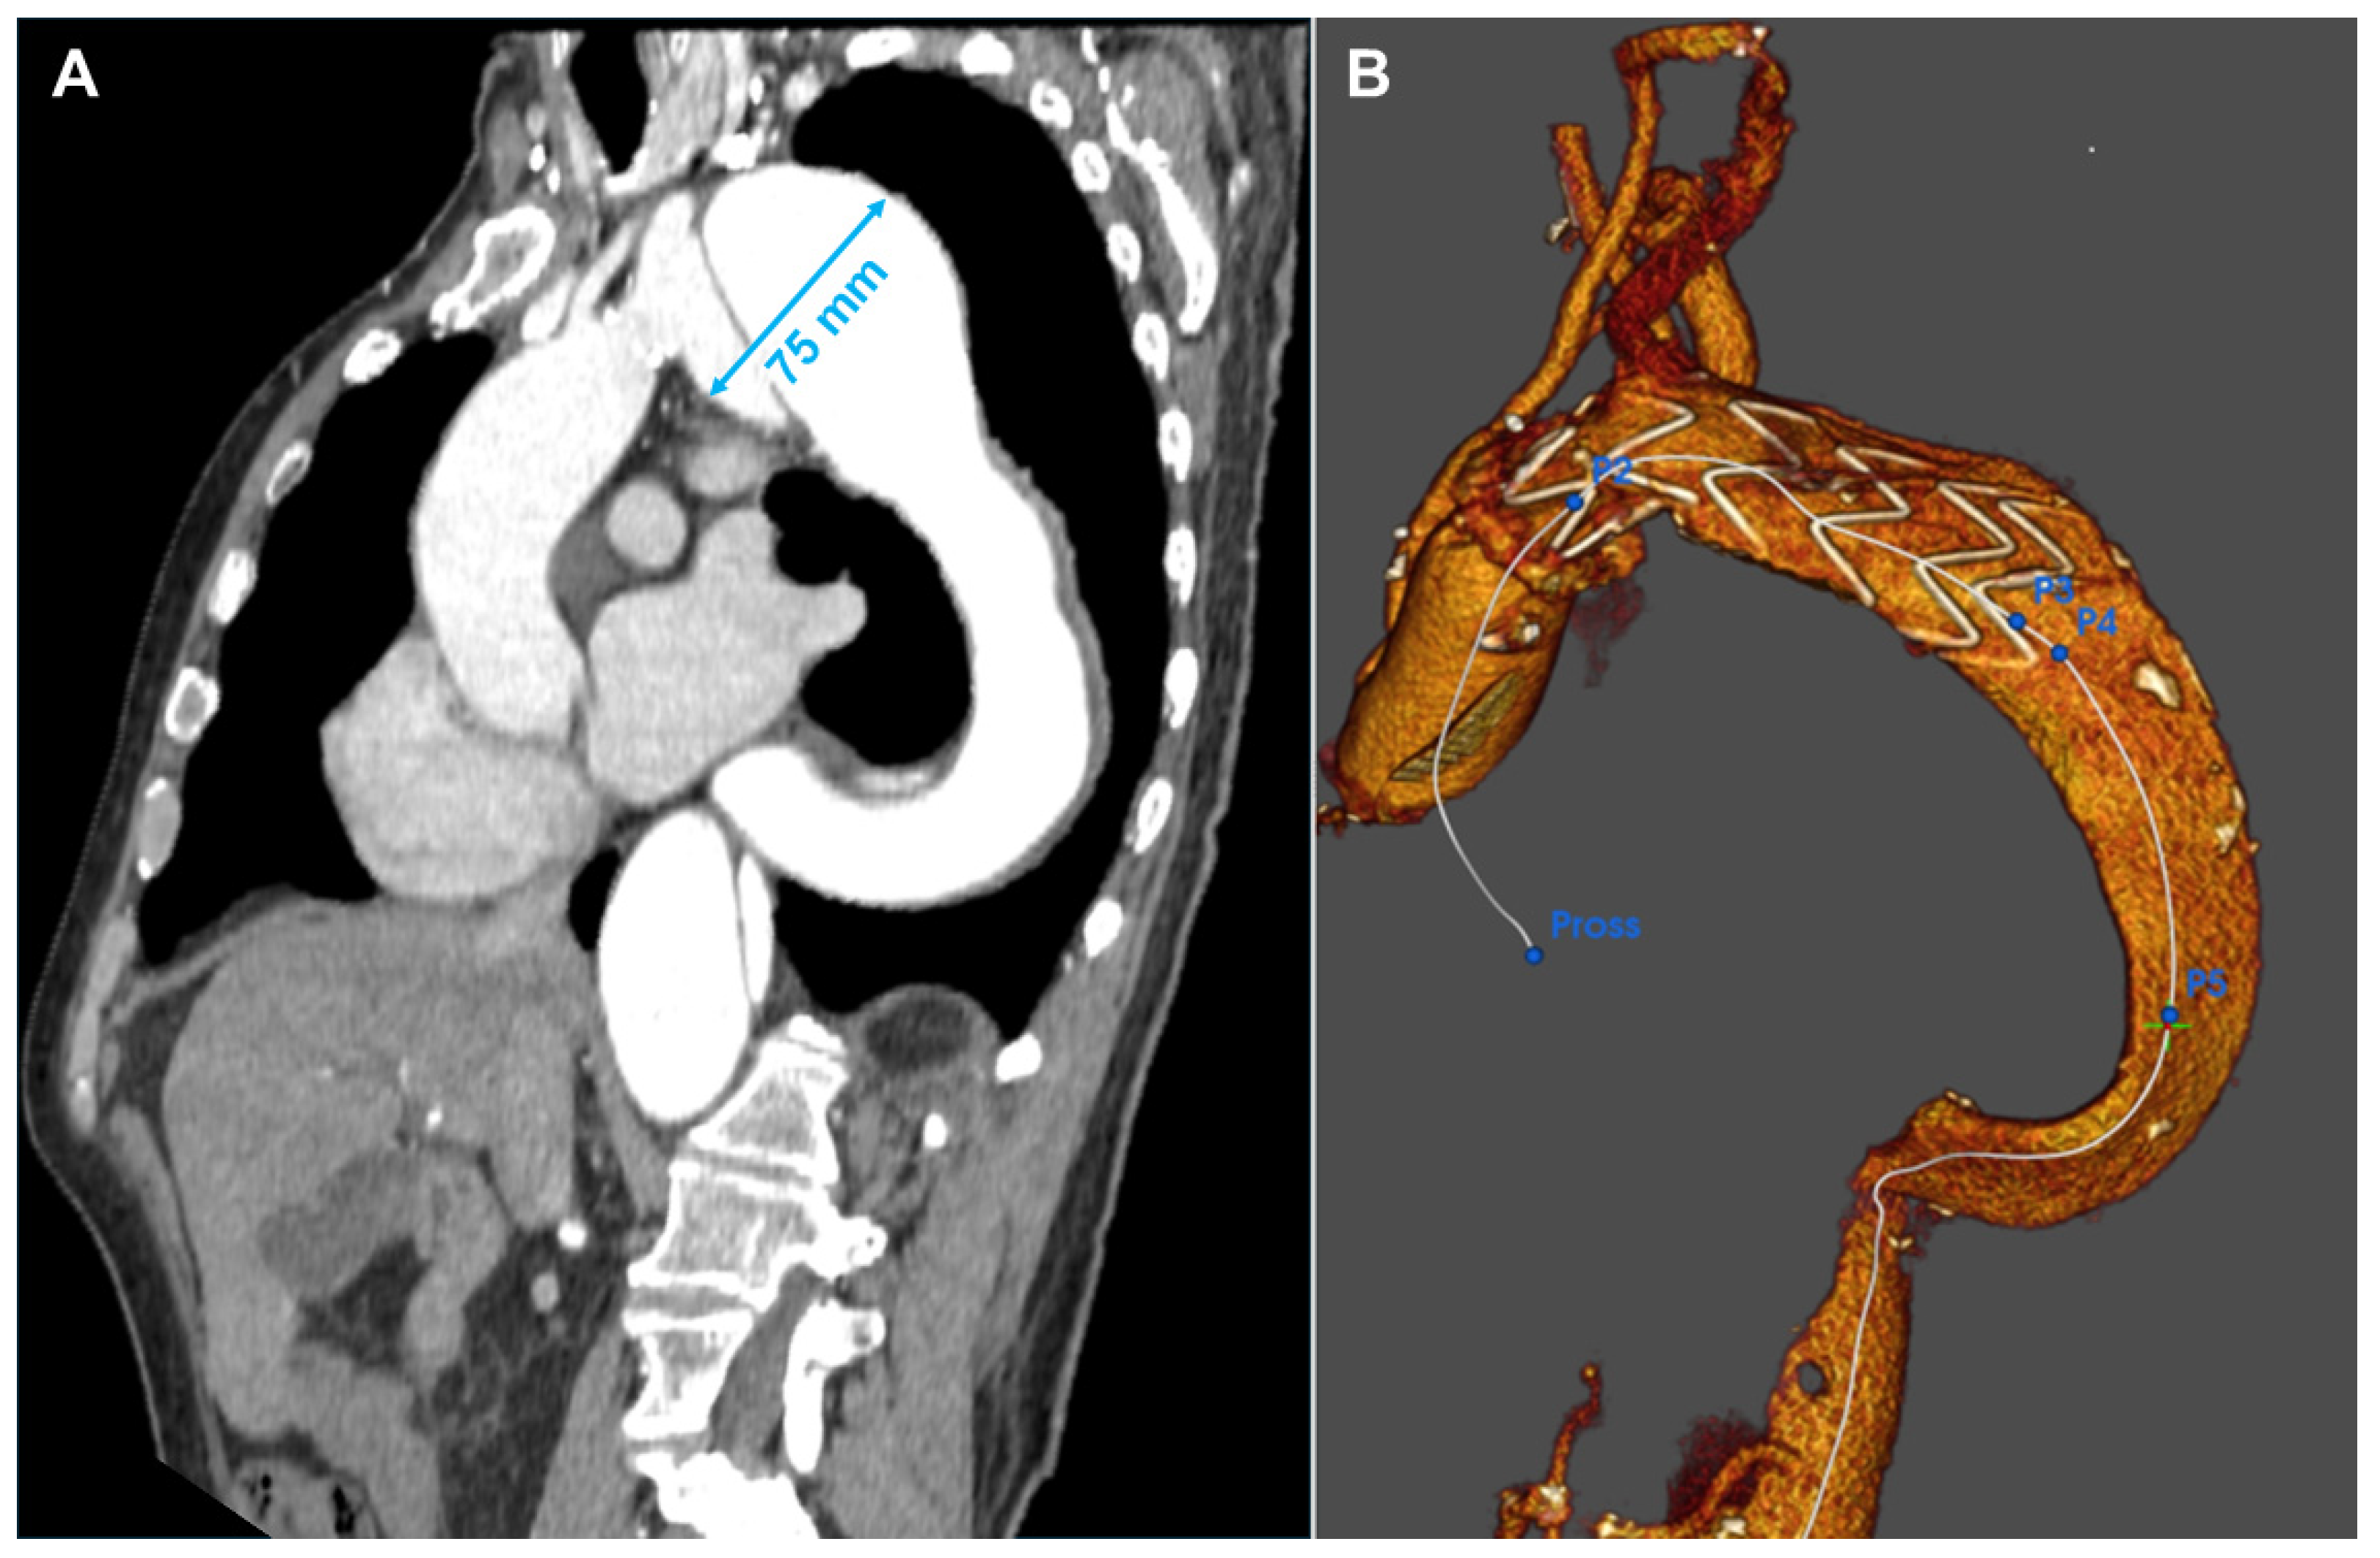

A 66-year-old gentleman presented with an aneurysm of 75 mm of the distal aortic arch and proximal descending thoracic aorta just below the origin of the subclavian artery, in the context of chronic type B aortic dissection previously managed conservatively. Further dilatation of the descending thoracic aorta with kinking at the diaphragm made the anatomy more challenging. Aneurysmatic dilatation of the ascending aorta precluded an endovascular option alone. Therefore, aortic arch replacement was considered a suitable approach [6]. A left common carotid–left subclavian artery extra-anatomical bypass was performed, followed by a frozen elephant trunk (FET) with Jotec E-Vita Open Neo 30-120 × 30 prosthesis 24 h later. The innominate and left common carotid arteries were re-implanted. Finally, significant disease of the left anterior descending coronary artery required grafting with the left internal mammary artery. The patient’s aortic pathology was further complicated by severe peripheral vascular disease, including total occlusion of the left external iliac artery and the right common iliac artery originating from the false lumen. Despite the unfavorable anatomy, a TEVAR (Terumo Relay Pro 32 × 32 × 155 mm) was performed, extending the distal landing zone to prevent caudal endoleak formation and exclude the aortic aneurysm. To address the type II endoleak originating from the left subclavian artery, a vascular plug was placed at its aortic origin, which completed the false lumen thrombosis of the Zone 4 aneurysm and the descending aorta. After a long and complicated postoperative course, the patient was discharged and continued with regular CTA follow-up, demonstrating clinical and anatomical stability (Figure 3).

Figure 3.

Patient 3’s Computed Tomography Angiography showing the evolution of the type B dissection with an enormous aneurysm of 75 mm in Zone 3 (A). Three-dimensional reconstruction of the result after the frozen elephant trunk operation (B). After one month, the patient was treated with another TEVAR in the descending aorta.